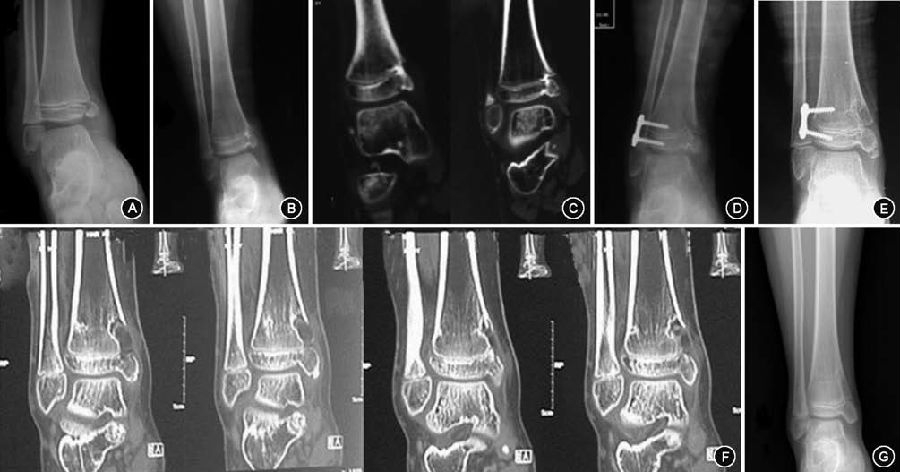

图1 10 岁男性股骨远端骺早闭,术前影像与术中导航相匹配 1A.术前X 线片显示股骨远端偏内侧骺早闭,形成中央型骨桥;1B.术前磁共振示在矢状位和冠状位上骺线中断,骨桥形成;1C.术中导航影像清晰显示出冠状位、矢状位、水平位的骨桥位置,图中所指为磨钻到达位置,引导下进行磨除  图2 11岁男性胫骨近端骺早闭,术前影像及术中骨桥磨除后再次导航确认 2A.受伤3 年后逐渐出现胫骨近端内翻畸形,术前平片未发现明确骨桥;2B.术前CT 检查发现胫骨近端部分层面可见边缘型骨桥;2C.术中磨除骨桥后再次导航,骨桥部位已变成空腔,术中应用指示器于空腔内各点确认骨桥完全磨除

图3 7岁男性胫骨远端骺早闭,术前影像及术后随访 3A.外伤造成胫骨远端内侧骺损伤,原始损伤时的X线片;3B.伤后8个月出现踝内翻畸形,术前X线显示形成边缘型骨桥,内踝形态异常;3C.术前CT证实胫骨远端内侧存在骨桥; 3D.导航下行胫骨远端内侧骨桥切除,外侧“8”字钢板固定,手术后平片; 3E.术后10个月畸形矫正,骨桥消失,内踝形态基本正常;3F.取出“8”字钢板后行CT检查,证实骨桥已被空腔替代,同时空腔向干骺端生长证明局部具有生长潜力; 3G.术后16个月复查,踝关节形态基本正常